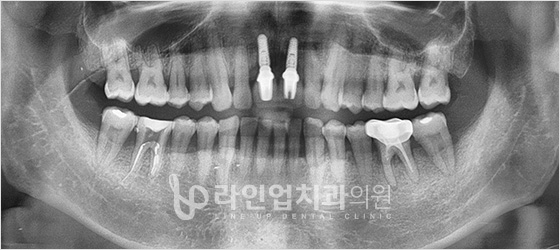

치료전

Before

치료후

After

앞니 임플란트 (42세/여/ 2015.09.14 ~ 2015/12.07)